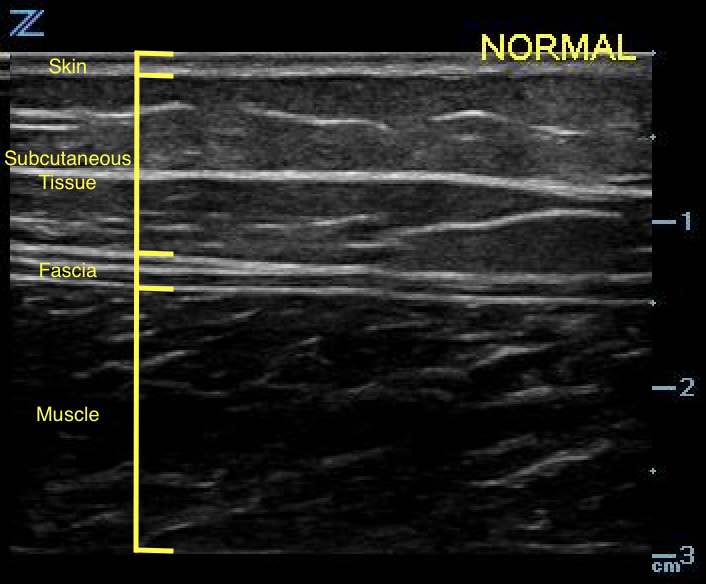

- With the equipment typically used for bedside ultrasonography, the epidermis and dermis cannot be differentiated. They appear together as a thin, hyperechoic layer.3

- The subcutaneous layer appears hypoechoic on ultrasound, with two components: hypoechoic fat interspersed with hyperechoic linear echoes running mostly parallel to the skin, which represent connective tissue septa (Fig. 2).3

- Figure 2. Normal skin, subcutaneous tissue, and fascia

- Fascia appears as a linear hyperechoic layer. Its thickness will vary depending on the location.4